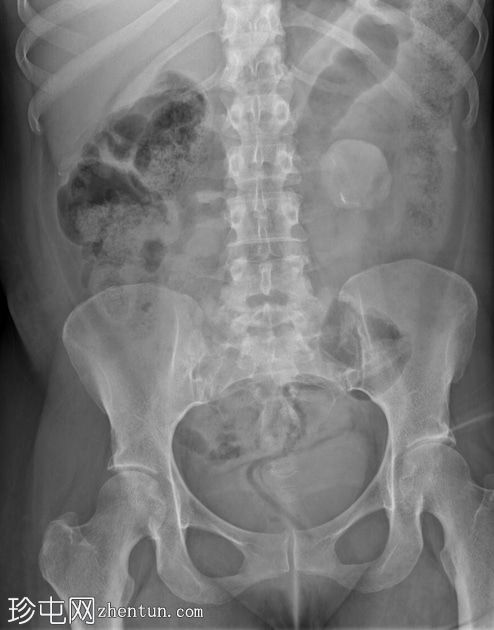

正位片

腹部X线片显示左侧腹部上方有一处边界不清的软性密度影。这代表已知的结肠造口和左侧腹部造口。

进一步发现非解剖性透亮区。这代表结肠造口袋。

可见少量粪便潴留。

PACS系统回顾既往腹部和盆腔CT的代表性图像证实了结肠造口和左侧腹部造口的存在,这解释了腹部X线片上发现的假瘤样改变。在三维皮肤表面图像上也可以看到结肠造口袋的轮廓,这解释了腹部X光片上出现的非解剖性透亮区。

在这种情况下,如果没有结肠造口史,腹部X光片可能难以解读。这种不寻常的局限性不透光区可能是伪影,如果没有侧位片或进一步的CT成像,就无法确定其起源于腹腔内还是腹腔外。

结肠造口和造口是导致腹部X光片上出现假瘤样表现的原因。